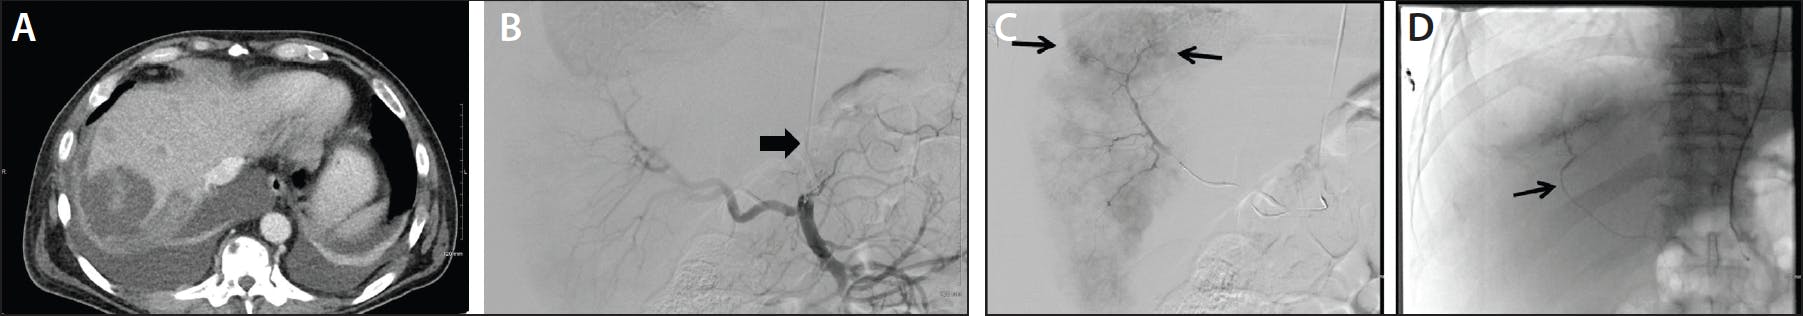

Figure 3. A woman in her early 40s presented with a newly diagnosed metastatic neuroendocrine pancreatic tumor with infiltration of the stomach and spleen, with anemia (hemoglobin, 5.7 g) and melena. Esophagogastroduodenoscopy showed a large, ulcerated vascular lesion in the gastric cardia but no exposed vessels or active bleeding. Axial (A) and coronal (B) CTA images of the abdomen with pseudoaneurysm of the splenic artery at the hilum (arrow). Interventional radiology was consulted for embolization. DSA via celiac access a using 5-F Sarah catheter (wide arrow) via left radial access showing a large splenic artery pseudoaneurysm at the splenic hilum (thin arrow) (C). After coil embolization (DSA and native overlayed) with no further filing of the pseudoaneurysm (D). While the patient had no further hematemesis or melena, she did experience postembolization splenic infarction given distal embolization.